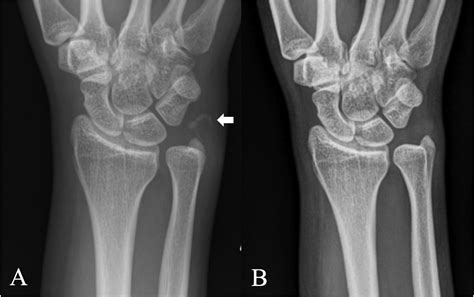

HADD can affect various joints, including the shoulder, elbow, wrist, hip, knee, and ankle. It can also occur in soft tissues such as tendons and ligaments. The most commonly affected areas are the shoulder and the wrist.

• Imaging Studies: X-rays, ultrasound, and magnetic resonance imaging (MRI) can help identify the presence of hydroxyapatite crystals and assess the extent of the deposits.

Imaging studies are particularly important in diagnosing HADD. X-rays can show calcifications in the affected areas, while ultrasound and MRI provide more detailed images of the soft tissues and joints. Laboratory tests can help rule out other conditions that may cause similar symptoms.